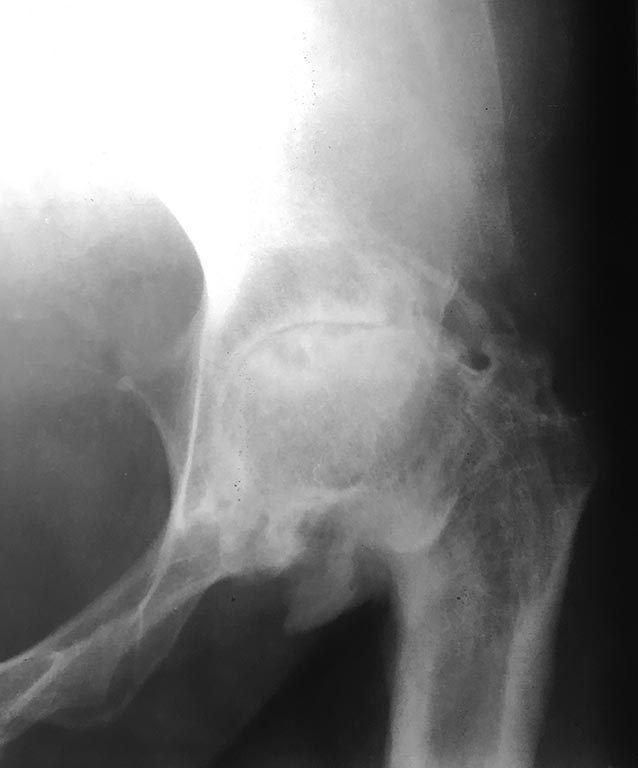

Пациентка 38 лет, жалобы на ограничение движений, боль в области

тазобедренного сустава, укорочение конечности, хромоту.

В возрасте 6 лет открытое вправление пропущенного врожденного вывиха

левой бедренной кости, осложнившееся кокситом. На данный момент:

Сгибательная приводящая установка в суставе, движения отсутствуют.

Обращает на себя внимание втянутый рубец, плотно спаянный

непосредственно с костью в области большого вертела без подлежащих

мягких тканей.

Больная настаивает на эндопротезировании. Пункция т/бедренного сустава:

без роста. С реактивный белок отрицательный.

╚ Костный этап ╩ больших вопросов не вызывает, а вот состояние мягких

тканей и перспективы оставить протез ╚ под кожей ╩ несколько смущают.